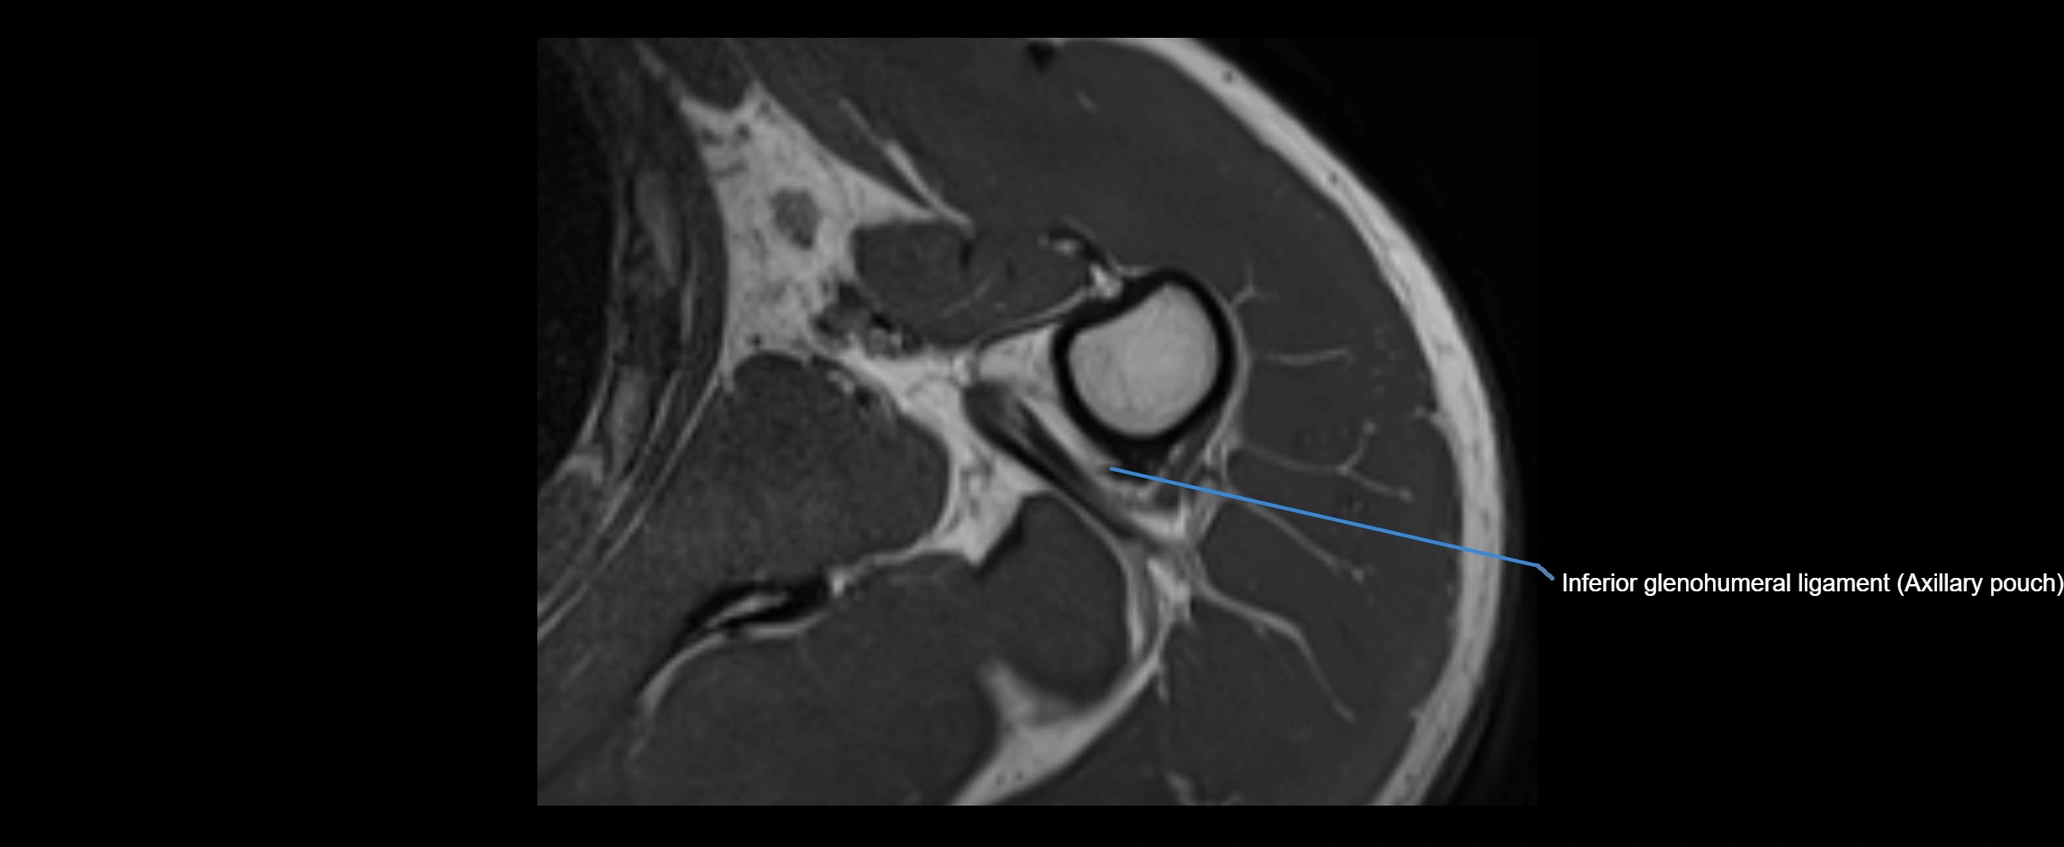

MRI images

image